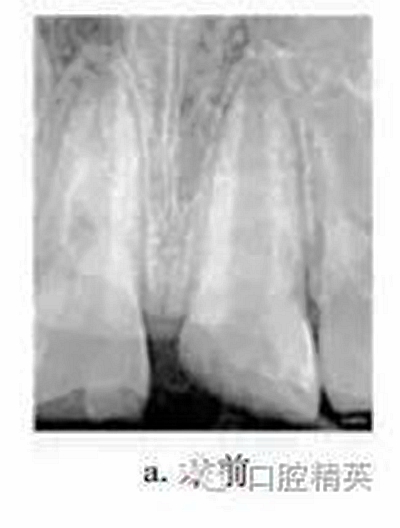

患者男,10歲。2011-06因上頜中切牙外傷就診于我院牙體牙髓病科。患者自述3d前患牙外傷,冷熱刺激敏感,但未行治療。檢查:11牙冠近中切角缺失,切緣釉質(zhì)缺損,無松動,探敏感,叩(+),冷熱無明顯不適;21牙冠近中斜折,邊緣銳,髓腔暴露,探診出血,探痛明顯,牙髓電活力測試(-),叩(+),無松動,牙齦未見異常,上唇腫脹。X線片示:21冠部缺損及髓,牙周膜腔增寬,根端管壁呈平行狀,根尖孔未閉合(圖a)。診斷:11釉質(zhì)缺損;21冠折。